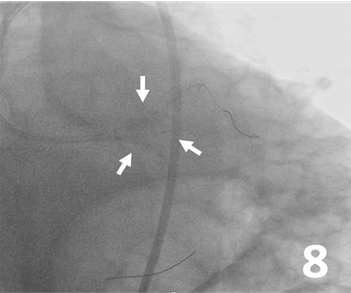

Predilatation was made from the LAD, ramus, and LCx to the left main artery with 3 Ryurei balloons (Terumo) at 8 atm (3.5 x 20 mm, 2.5 x 20 mm, and 2.5 x 15 mm, respectively) (Figure 5). A 3.0 x 32-mm synergy stent was deployed from the middle to the proximal segment of the LAD (Figure 6). Then, 3 stents were advanced and deployed simultaneously from the LAD, ramus, and LCx (Synergy 5.0 x 24 mm [Boston Scientific], Xience Sierra 3.0 x 33 mm [Abbott], and Synergy 3.5 x 16 mm, respectively) (Figure 7). Simultaneous triple-balloon (kissing) inflation at 12 atm was performed with three 2.0 x 15-mm Ryurei balloons (Figure 8); the 3 balloons were simultaneously inflated 3 times.